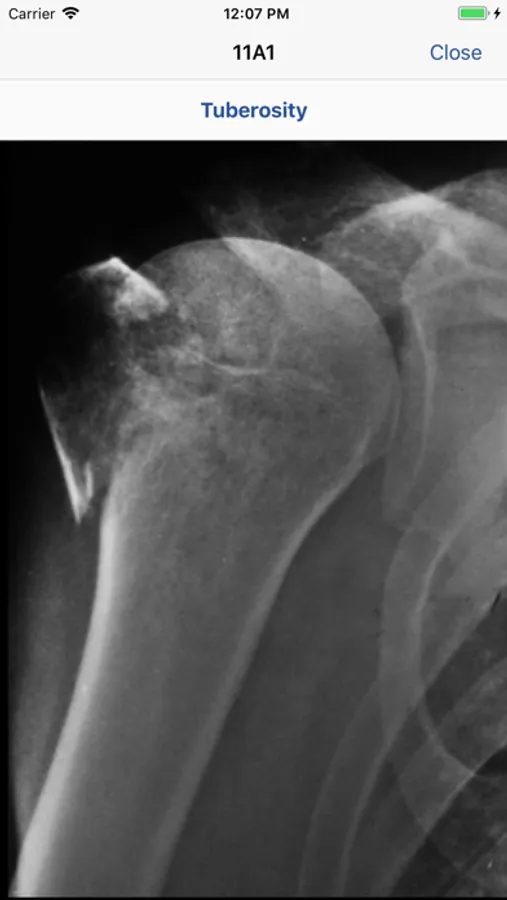

The 2018 AO/OTA Fracture and Dislocation Classification is a streamlined, concise, and clinically relevant tool for coding fractures and dislocations.

It is the standard classification used by trauma surgeons and physicians dealing with skeletal trauma worldwide. The Classification was revised in 2018 and the new app was updated to reflect these changes.

The content and design of the app makes the Classification simpler to use. The AO/OTA Classification app makes injury descriptions more reliable, thus improving research and fracture outcomes assessments.

• Information regarding radiological investigations used for classifying a specific fracture

• Common pitfalls with imaging are addressed

• High-quality, enlargeable x-rays are included